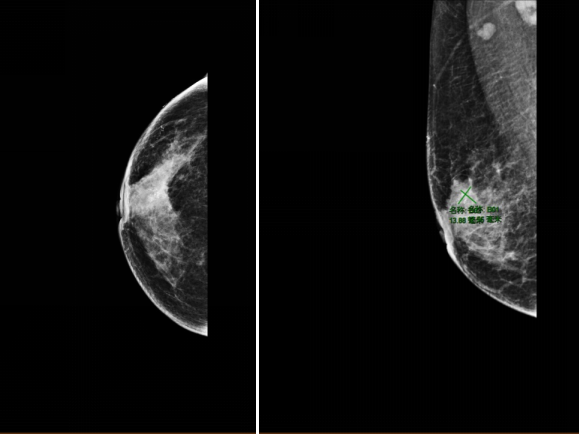

2021-11-30,钼靶:右乳外上象限较高密度肿块影,有浅分叶,约1.4×1.3cm大小,其内及邻近簇状分布细小多形钙化,符合乳腺癌诊断,BI-RADS 6类。右腋下见增大淋巴结影,约1.8cm直径大小。(图1)

图1.钼靶(2021-11-30)